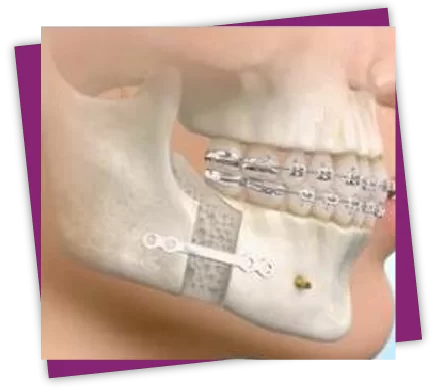

Bác sĩ sẽ dùng thiết bị máy cắt xương chuyên dụng để tác động đến phần xương, cắt đẩy lùi hàm dưới về sau có thể kết hợp kéo xương hàm trên về phía trước để làm khít khớp cắn.

Nếu móm mức độ trung bình: Phẫu thuật cắt xương hàm dưới trượt về sau (phương pháp BSSO) để làm khít khớp cắn.

Nếu móm nặng, hai hàm xa nhau quá nhiều: Phẫu thuật cắt xương hàm dưới đẩy lùi về sau (BSSO) và cắt chỉnh xương hàm trên kéo đưa về phía trước (Phương pháp Lefort I).

Sau khi chỉnh sửa vị trí tối ưu của 2 hàm, xương được cố định lại bằng nẹp vít cứng chắc, mang đến sự cân đối cho hai hàm, khớp cắn khít nhau, hỗ trợ việc ăn nhai.